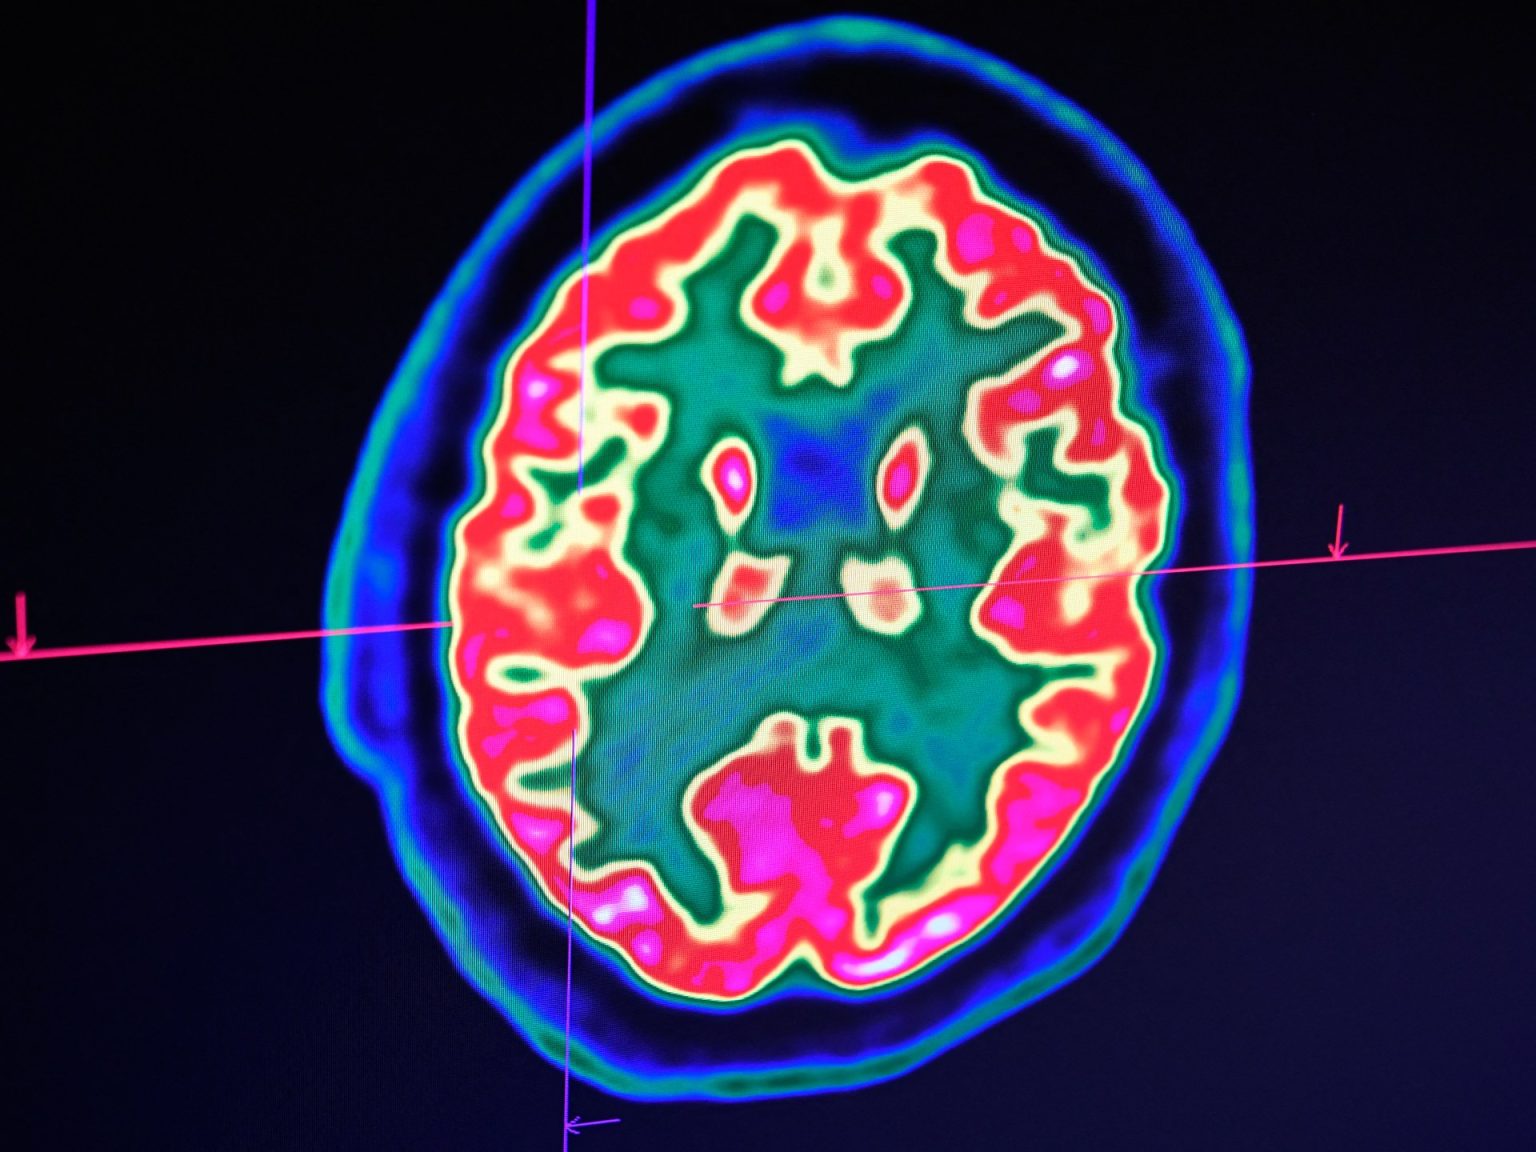

ويقول إنه في دراسة مجلة تقارير علمية -التي تحدثنا عنها سابقا- قدم علماء الأعصاب أول دليل تجريبي على أن بعض الأشخاص لا يزال بإمكانهم السماع أثناء وجودهم في حالة عدم الاستجابة قبل ساعات من الموت. وباستخدام مؤشرات تخطيط أمواج الدماغ (EEG)، قام علماء الأعصاب في جامعة كولومبيا البريطانية بقياس النشاط الكهربائي في الدماغ لدى مرضى دار العجزة في مستشفى سانت جون عندما كانوا واعين وعندما أصبحوا غير مستجيبين.

كما تم استخدام مجموعة مراقبة من المشاركين الشباب الأصحاء. راقب الباحثون استجابات الدماغ للنغمات ووجدوا أن الأنظمة السمعية للمرضى المحتضرين استجابت بشكل مشابه لمجموعات المراقبة الشابة والأصحاء بعد ساعات فقط من نهاية الحياة. وخلصوا إلى أن الدماغ المحتضر يستجيب للنغمات الصوتية حتى أثناء حالة اللاوعي، وأن السمع هو آخر حاسة تدخل في عملية الموت.